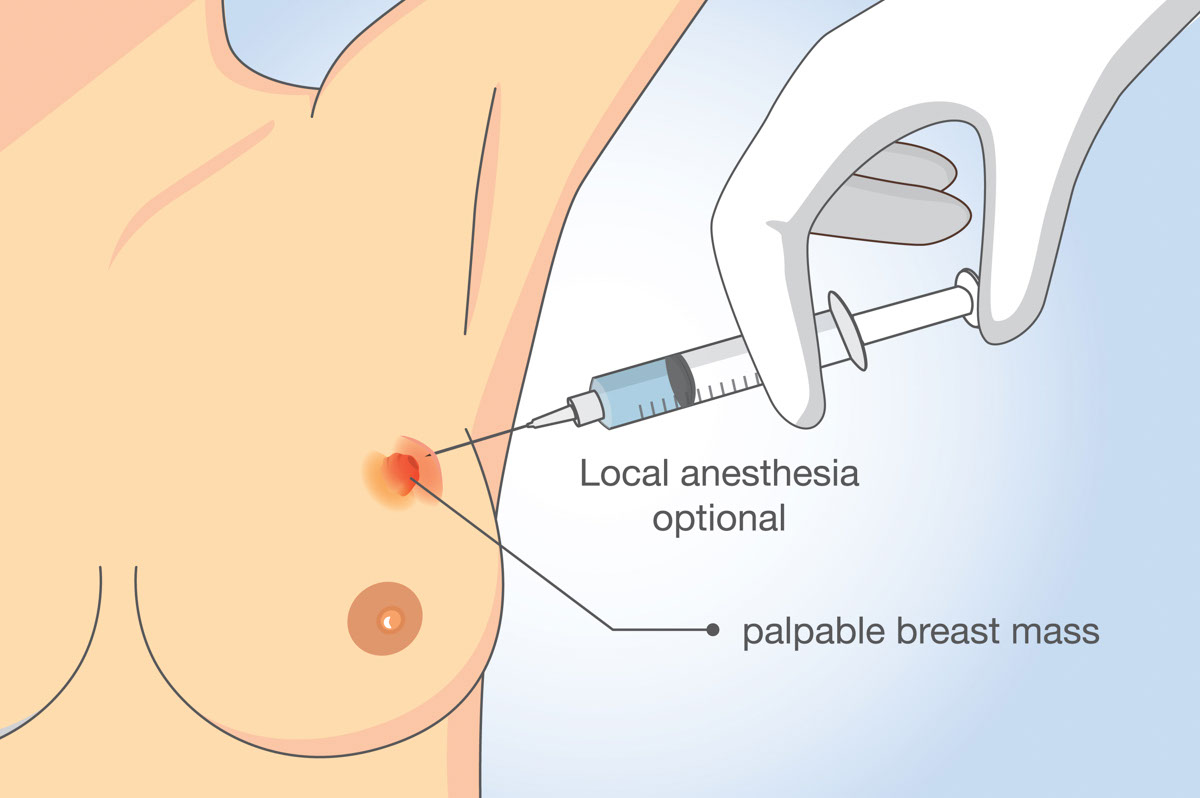

(1) 針刺細胞檢驗 (Fine Needle Aspiration)

針刺細胞檢驗是一種快捷簡便和安全的細胞檢驗方法,能對各種病變/腫瘤作出有效的診斷,俗稱 「細針」 抽取。 用於較為表淺、可以輕易抽取的組織, 例如是頸部淋巴結、甲狀腺、表皮腫瘤又或者乳癌等等。

好處是副作用輕——由於針細所以抽取後流血較少;不好處是這種方法只可以看得到細胞狀態 (cytology) ,而看不到癌細胞之間的紋理結構 (architecture)。

這種方法現在主要用於初步診斷。